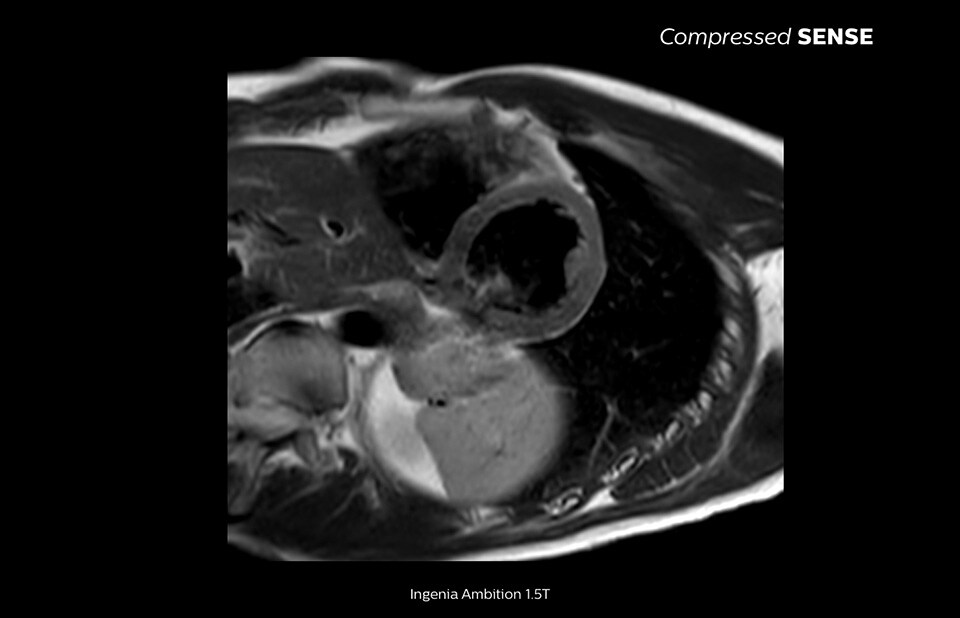

Compressed SENSE acceleration software - Philips